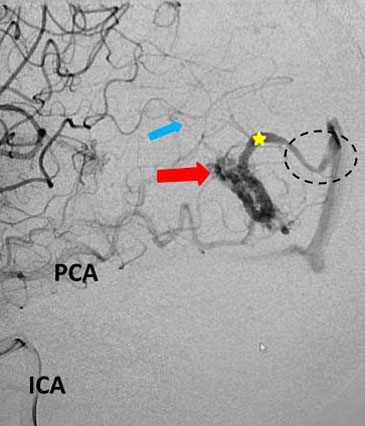

Fig 5. Comparison, pre (5A) and post-embolization (5B) AP view, late-arterial phase of a right internal carotid artery (ICA) injection. On the right, near total obliteration of the AVM (red arrow). Draining vein (yellow star), residual veins (blue stars).

The student underwent NBCA-embolization of the AVM via the dominant feeding posterior cerebral artery with care to avoid embolizing the calcarine branches and avoid NBCA penetration into the single draining vein (Fig 4 and 5). Following the intervention, a tiny feeder from the middle cerebral artery remained (Fig 4).